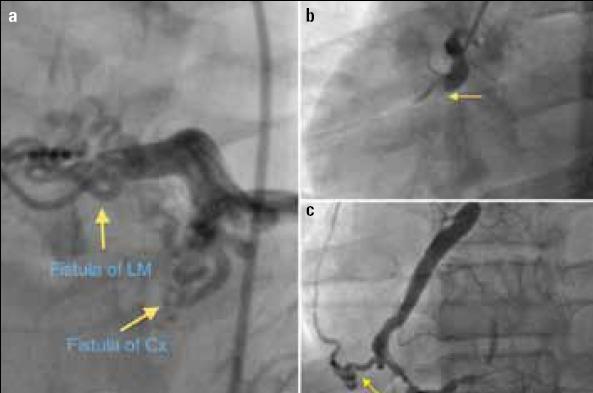

Multiple coronary artery fistulae presenting with ST-elevation myocardial infarction.

Image. Bicoronary-pulmonary fistulae and acute coronary syndrome.